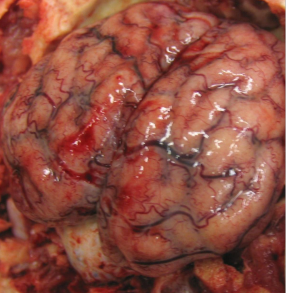

What is this in a cow? Diagnostic test.

Cerebrocortical necrosis

Autofluorescence under UV light